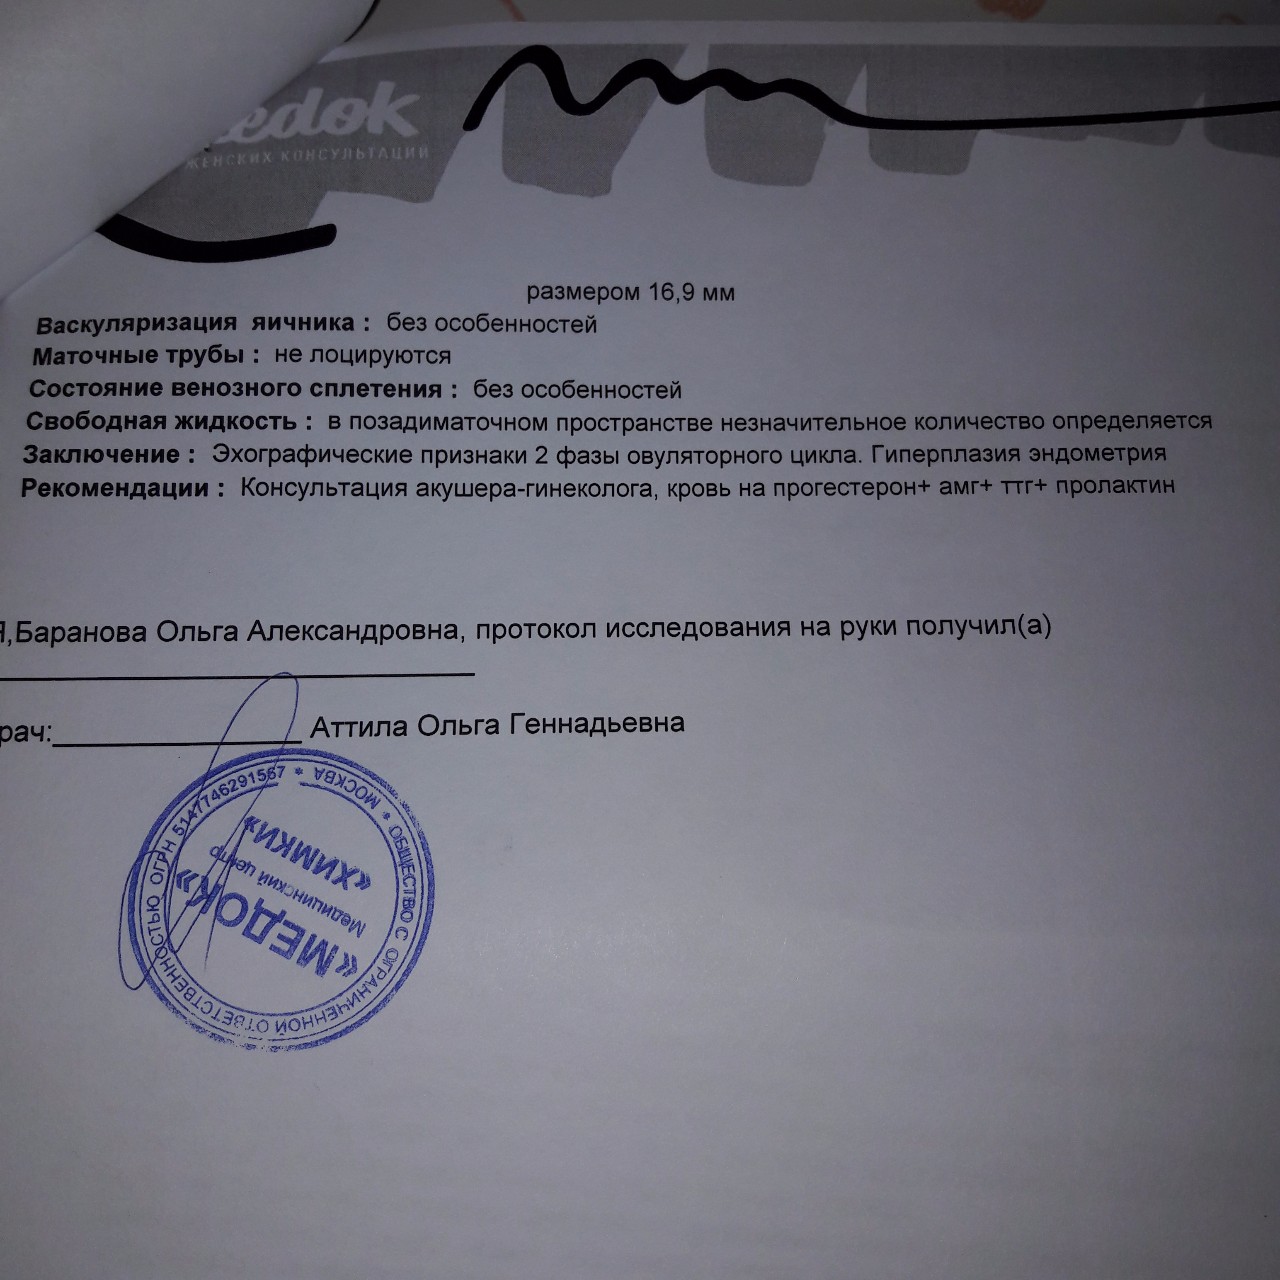

Медицинская диагностика: Гиперплазия эндометрия на УЗИ